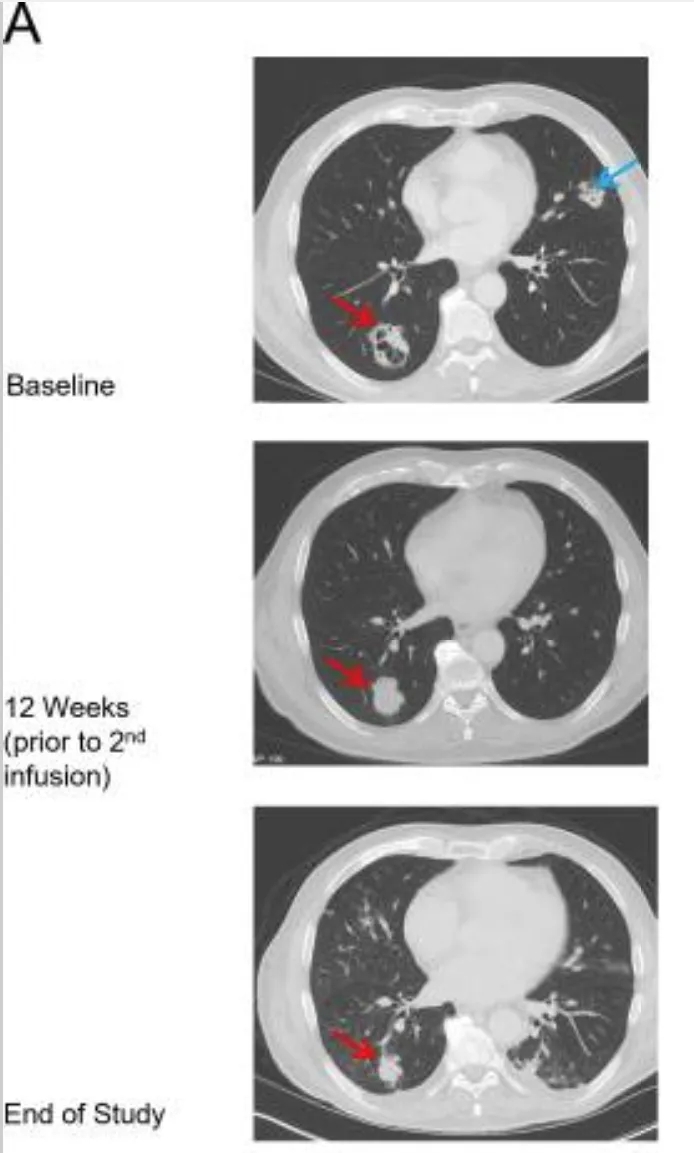

值得一提的是,患者9对治疗有反应且ADP-A2M10持续存在。在首次输注后肿瘤缩小25%,随后接受第二次ADP-A2M10输注;第二次输注8周后,与基线相比实现经确认的部分缓解(PR)(详见下图A、B)。

▲图源“J Immunother Cancer”,版权归原作者所有,如无意中侵犯了知识产权,请联系我们删除

注:

①红色箭头:代表肺右下叶(RLL)肿块。

②蓝色箭头:代表肺左上叶(LUL)肿块。